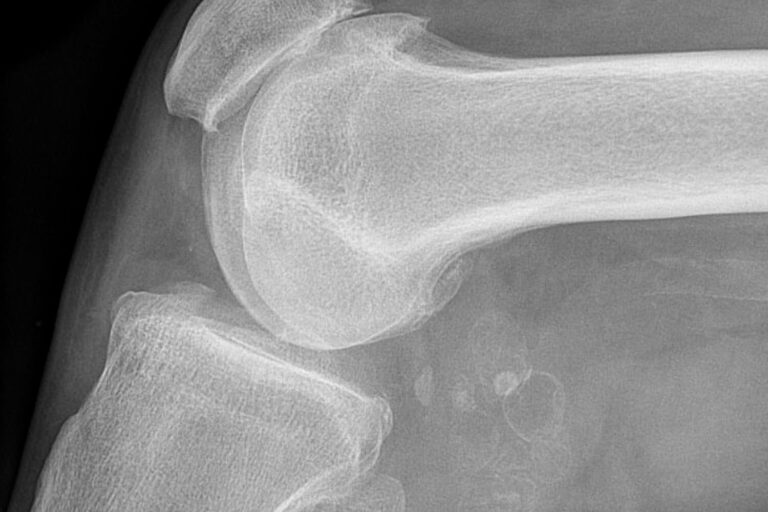

Gonarthrose, injections intra-articulaires et arthroplastie

Les anomalies de la coiffe des rotateurs sont-elles des incidentalomes ?